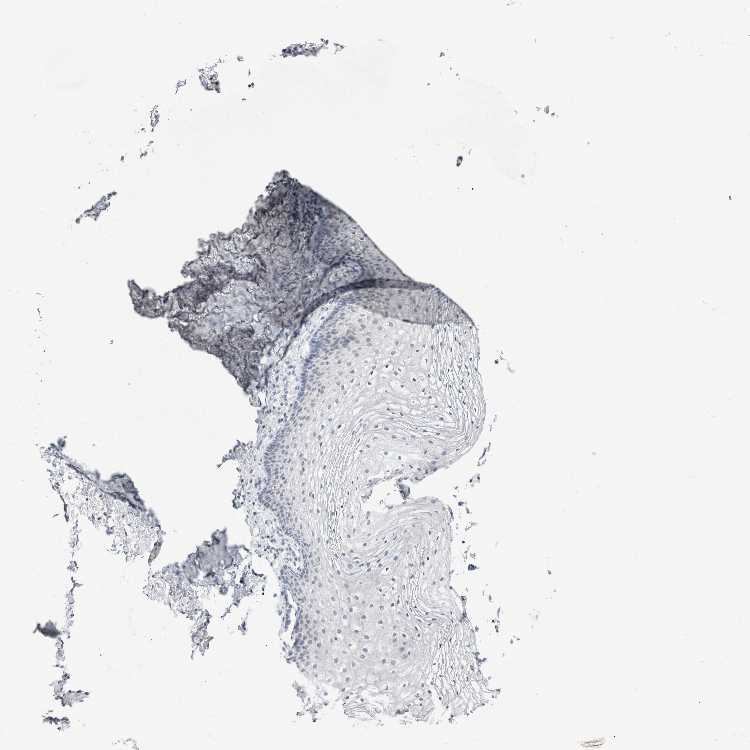

TISSUE PRIMARY DATA VAGINA Show tissue menu

VAGINA - Antibody stainingi

Antibody staining in the annotated cell types in the current human tissue is reported as not detected, low, medium, or high, based on conventional immunohistochemistry profiling in selected tissues. This score is based on the combination of the staining intensity and fraction of stained cells.

Each image is clickable and will lead to virtual microscopy that enables deeper exploration of all samples and also displays staining intensity scores, fraction scores and subcellular localization as well as patient and tissue information for each sample.

Antibody HPA011337Antibody HPA024303Antibody CAB003775

Squamous epithelial cells Not detectedNot detectedNot detected